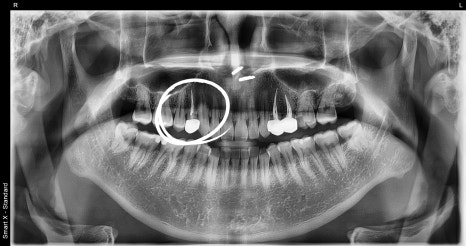

Photo after root canal treatment and crown treatment completed

After the nerve is removed, only the “shell” of the tooth remains.

The inside becomes hollow, so it is much weaker than before.

Molar teeth, in particular, receive a lot of force when chewing,

so the risk of breaking is high.

So,

the inside is reinforced with resin,

and on the outside,

a zirconia crown is placed as a strong cover for protection.

This is how a tooth that has had root canal treatment can be used for a long time.